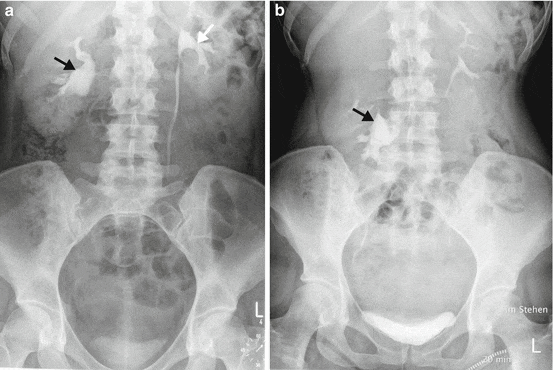

Основной метод диагностики нефроптоза–рентгенологическое и ультразвуковое исследования. Наиболее информативны инструментальные методы обследования почек - обзорный рентгеновский снимок мочевой системы, а также экскреторная урография - рентгеновский метод исследования, сочетающийся с введением контрастного вещества в вену больного. Снимки делаются в положении стоя и лежа. Радиоизотопные сканирование и сцинтиграфия позволяют определить положение, а ренография – функциональное состояние патологически подвижной почки. Ангиография позволяет судить о состоянии почечной артерии, венография - о венозном оттоке. Иногда приходится исследовать все органы желудочно-кишечного тракта (рентген желудка и кишечника, ФЭГДС, колоноскопия) для исключения или подтверждения общего опущения органов брюшной полости.